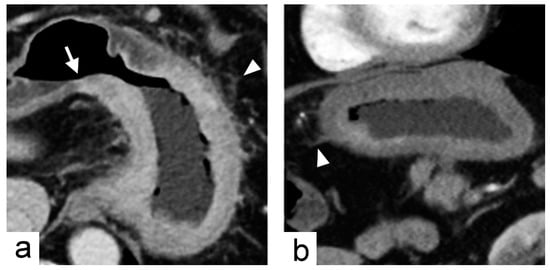

Figure 4. Non-chromosomal instability subtype gastric cancer in a 68-year-old male who underwent preoperative contrast-enhanced computed tomography. (a) portal venous phase axial and (b) arterial phase sagittal images showed extensive circumferential wall thickening involving the gastric fundus, cardia and body with the largest diameter of 6.6 cm. The tumor had obtuse tumor transition angle (arrow in (a)), ill-defined margin and infiltrative shape in morphology. Because of the peri-gastric stranding densities, the lesion was also defined to have “serosal invasion” imaging trait (arrowheads in (a,b)), which was later confirmed by histopathology analysis.